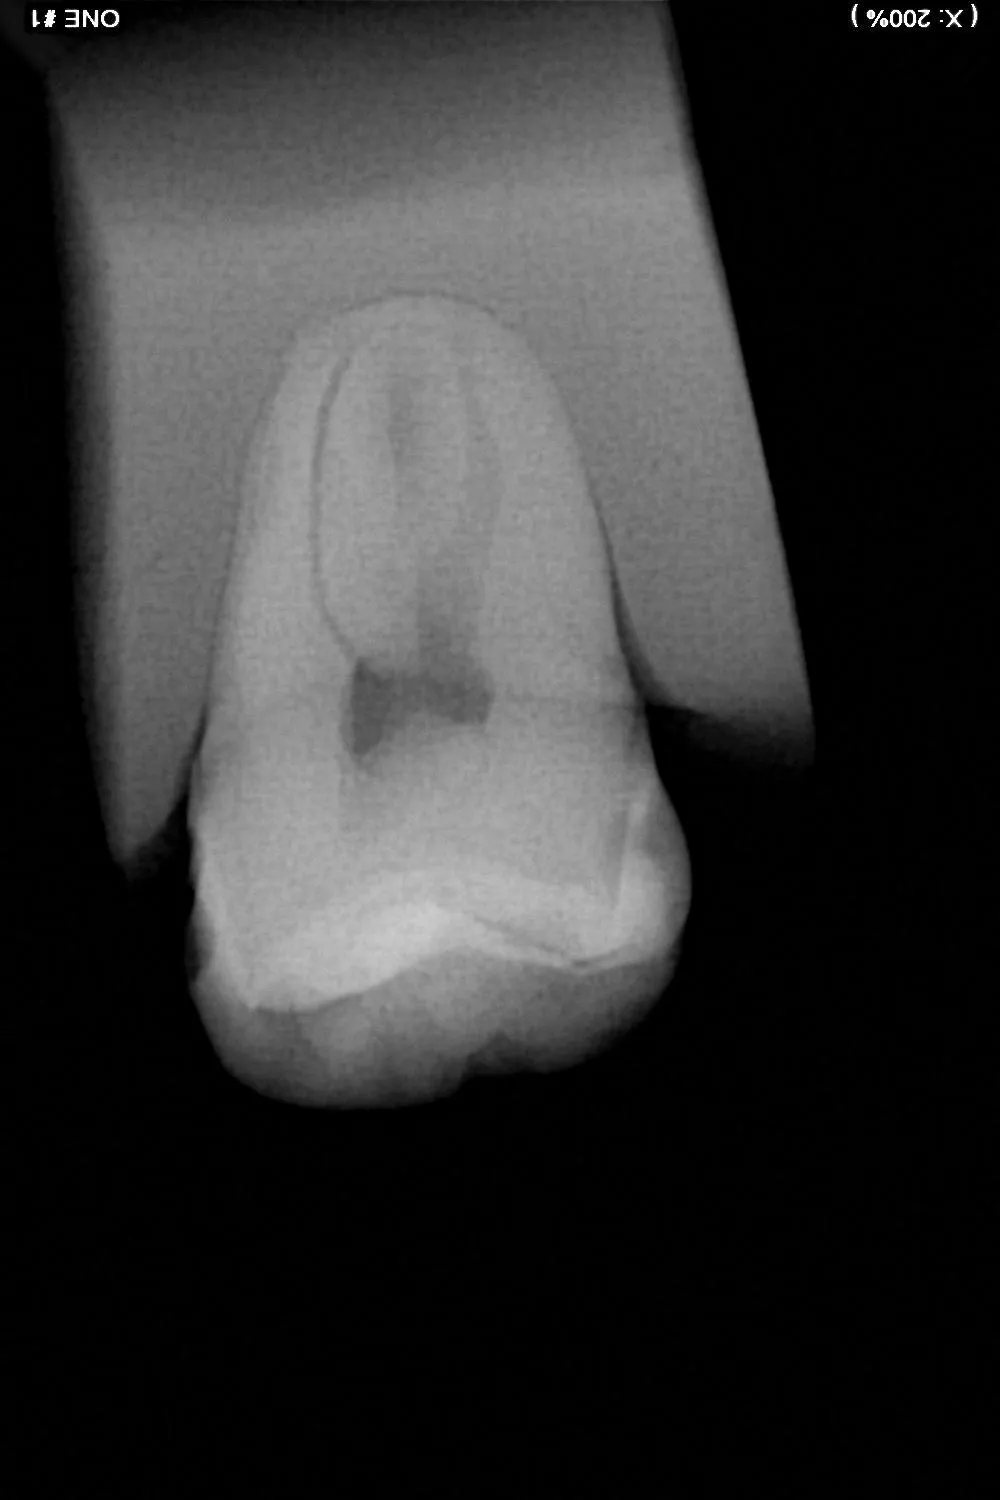

Le traitement endodontique vise à retirer la pulpe infectée, à nettoyer et désinfecter en profondeur les canaux radiculaires, puis à les obturer hermétiquement. Ce protocole minutieux, réalisé sous anesthésie locale, permet dans la majorité des cas d’éviter l’extraction, de soulager la douleur et de restaurer la dent sur une base saine.

Pour traiter l’infection, l’endodontiste doit accéder à la pulpe. Pour ce faire, il placera une digue autour de la dent, c’est un champ qui protège le site en cours de traitement, de la salive et de la langue, pour permettre une désinfection optimale de votre dent. Une ouverture est pratiquée sur la dent afin d’atteindre les canaux. Les tissus infectés sont alors retirés, puis les canaux sont soigneusement nettoyés à l’aide de limes K manuelles et de limes mécaniques type Protaper Gold et Reciproc, ainsi que d’une bonne irrigation des canaux à l’aide de plusieurs solutions désinfectantes (NaClo, EDTA, Chlorhexidine, sérum physiologique). Après séchage, les canaux sont obturés de manière étanche pour prévenir tout risque de recontamination par des bactéries. En fonction de l’état de la dent, une restauration adaptée est ensuite réalisée : soit une obturation classique, soit une couronne si la structure est fragilisée.